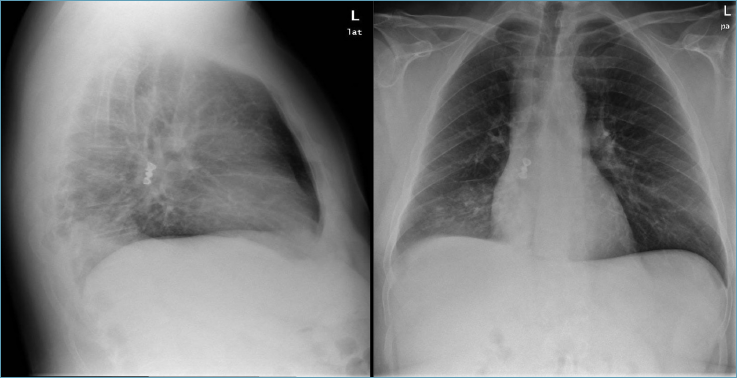

Un uomo di 51 anni, giungeva in Pronto Soccorso per rimozione accidentale di stent ureterale dx. In anamnesi si rilevavano: obesità, ipertensione, diabete tipo II, cardiopatia dilatativa con severa disfunzione ventricolare (FE 30%), calcolosi ureterale dx con idronefrosi e posizionamento di stent ureterale in attesa di intervento, OSAS di grado severo con indice apnee-ipopnee (apnea-hypopnea index, AHI) di 58h e insufficienza respiratoria (TST90 48%), in terapia con CPAP con interfaccia di tipo oronasale. Non erano presenti patologie e/o disordini di tipo neurologico. All’emogasanalisi arteriosa, si evidenziava ipossiemia (PaO2 59 mmHg), mentre la pressione parziale di anidride carbonica e l’equilibrio acido-base erano nei limiti (PaCO2 44 mmHg). L’Rx torace mostrava, in corrispondenza del bronco per il lobo inferiore destro, la presenza di protesi metallica, con disomogeneità polmonare post ostruttiva (Fig. 1). Da circa un mese il paziente riferiva di aver constatato la perdita di protesi dentaria (segmento di 3 denti) senza aver presentato sintomatologia correlata ad inalazione, eccetto la presenza di modesta tosse irritativa in rapporto alla postura.

Figura. 1.Rx torace nelle due proiezioni antero posteriore e laterale, con presenza di corpo estraneo metallico in bronco del LID, e addensamento parenchimale contestuale.